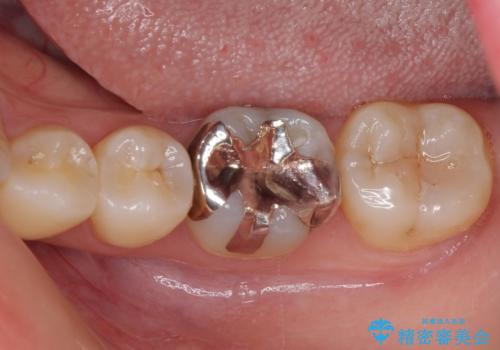

- 下の奥歯(右下7・左下7)にあって目立ってしまう銀歯を白くしたいとのことで来院された患者様です。

セラミックインレーにて修復治療を行うこととしました。